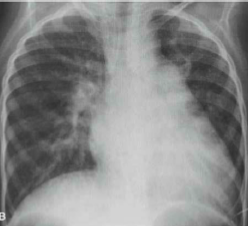

Com base no raio-x ilustrado a seguir, qual patologia é mais provável de ser encontrada?